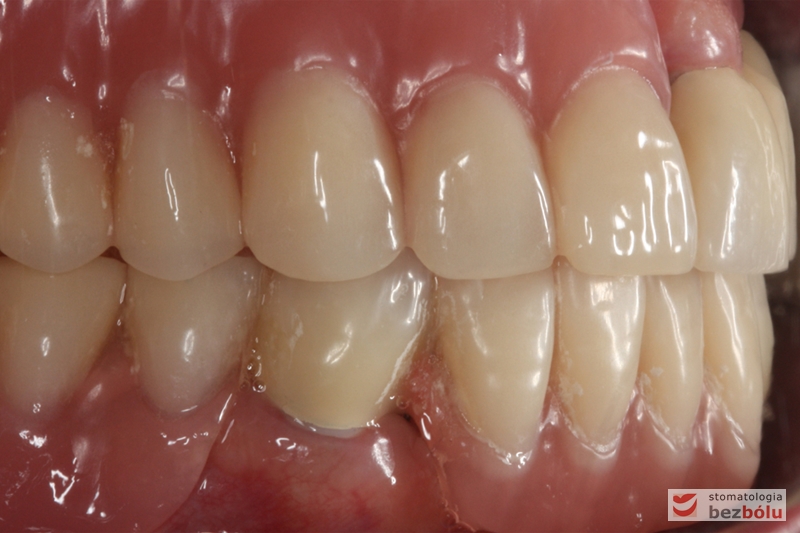

Efekt końcowy leczenia protetycznego

Ostateczny efekt terapeutyczny - zadowolona i uśmiechnięta pacjentka

Ostateczny efekt terapeutyczny – zadowolona i uśmiechnięta pacjentka